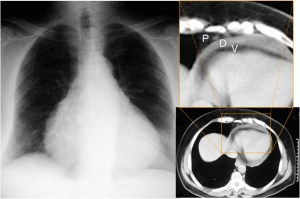

SIGNO DE LA ALMOHADILLA EPICÁRDICA (O SIGNO DE LA GALLETA OREO)

Signo de derrame pericárdico en la radiografía lateral de tórax. El derrame aparece como una banda curva de densidad agua que separa las capas grasas pericárdicas visceral y parietal a nivel retroesternal bajo.

La radiografía posteroanterior de tórax del mismo paciente muestra el aumento de tamaño de la sombra cardíaca con la morfología característica del derrame pericárdico (corazón en “tienda de campaña”). A la derecha, la imagen de TC con el derrame pericárdico (D) separando las capas grasas pericárdicas visceral (V) y parietal (P).

En la literatura en inglés, este signo es llamado «oreo cookie sign» por el aspecto de las capas hipo, hiper e hipodensa.